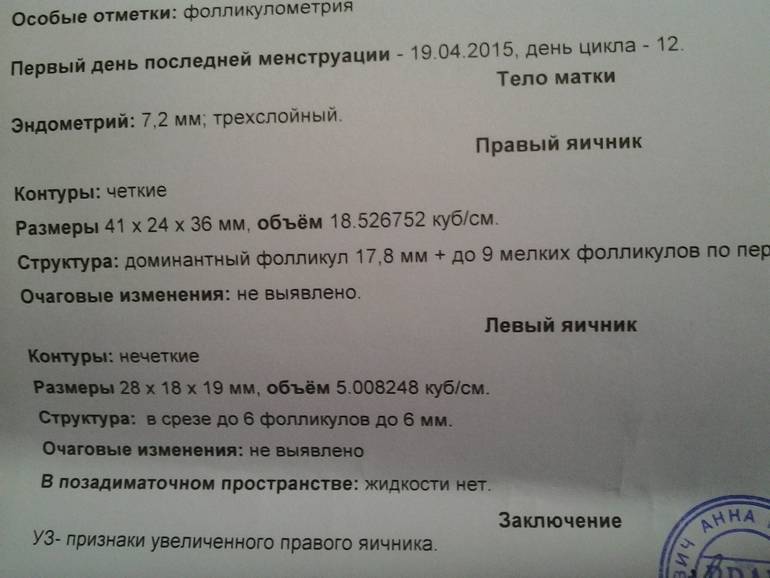

Созревание фолликула в яичнике: этапы и процессы